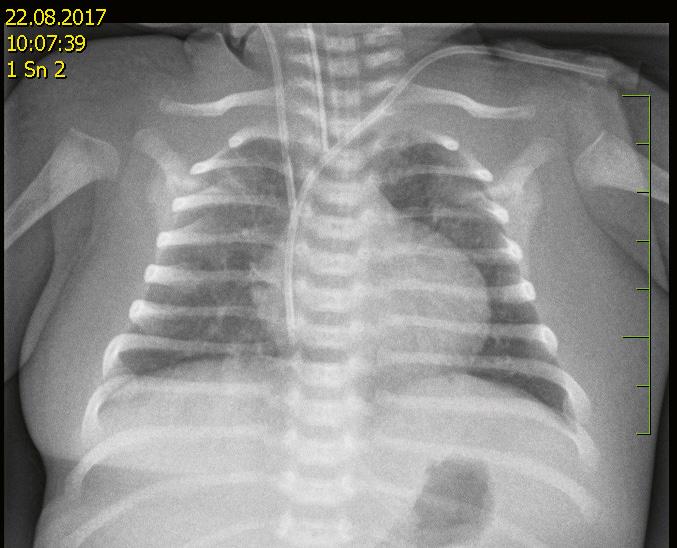

17 Poranění hrudníku (Martin Prchlík, Pavel Heinige) ..............................

17.1 Definice, charakteristika a popis stavu obecně

17.2 Etiologie, anamnestické údaje

17.3 Příznaky, vyšetření v rámci přednemocniční neodkladné péče

17.3.1 Zhodnocení celkového stavu pacienta ..........................................

17.4 Diferenciální diagnóza ...................................................................................

17.4.1 Neúrazové příčiny bolesti na hrudi nebo dechové tísně, které je třeba diferenciálně diagnosticky odlišit ...........................

17.5 Ošetření a léčba v rámci přednemocniční péče ..........................................

17.6 Případné poznámky k dalšímu ošetření a transportu ................................

17.7 Opatření v rámci převzetí dítěte s podezřením na poranění hrudníku na centrální příjem .......................................................................................... 206

17.7.1 Klinické vyšetření na urgentním příjmu ....................................... 206

17.7.2 Konziliární vyšetření u dítěte s podezřením na poranění hrudníku ............................................................................................ 207

17.7.3 Laboratorní vyšetření na urgentním příjmu u dítěte s podezřením na poranění hrudníku

17.7.4 Zobrazovací vyšetření dítěte s podezřením na poranění hrudníku v rámci centrálního příjmu

17.8 Co s pacientem dál ..........................................................................................